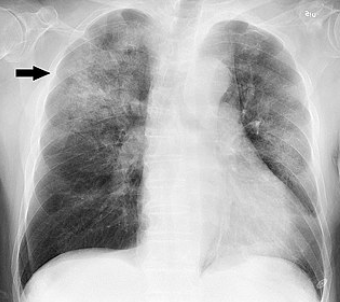

• "Chest radiograph in influenza and H. influenzae, posteroanterior"

• "Chest radiograph of an 88 -year-old man, about one week after onset of fever, fatigue, and mild coughing. Lab tests detected both influenza A virus and Haemophilus influenzae. It shows multifocal, patchy consolidation, mainly in the right upper lobe" (arrow).

• Mikael Häggström, M.D. Author info - Reusing images- Conflicts of interest:  NoneMikael Häggström, M.D.Consent note: Written informed consent was obtained from the individual, including online publication., CC0, via Wikimedia Commons